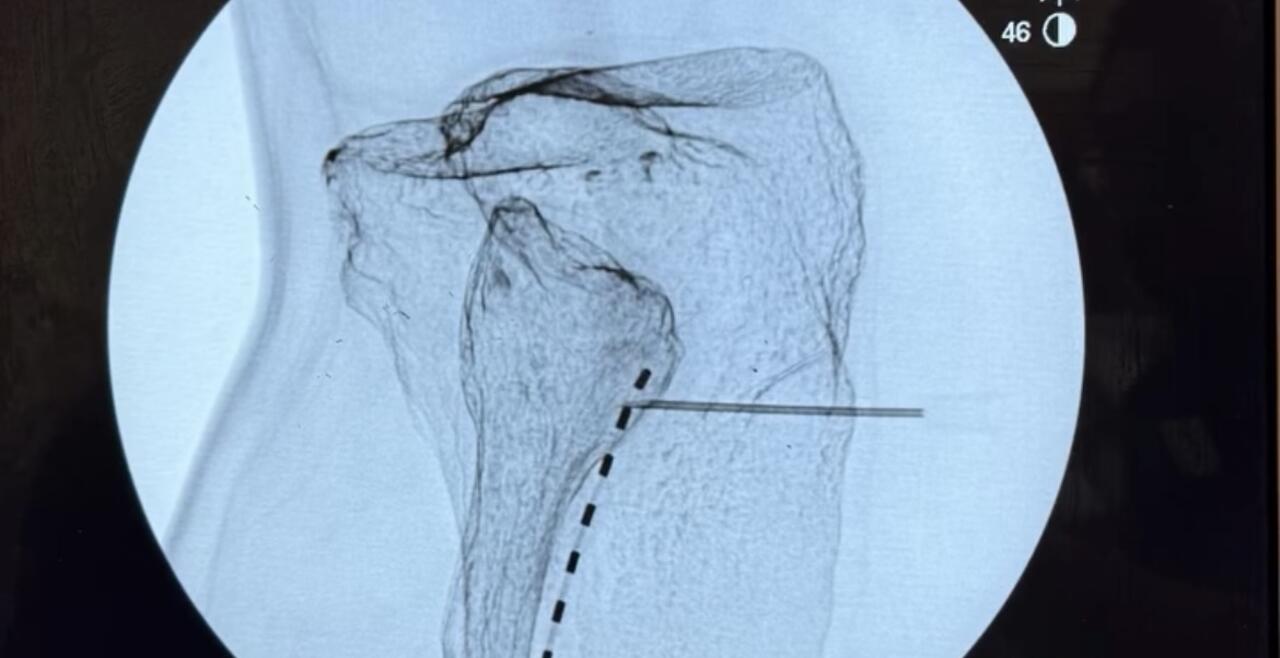

- Four onsite fluoroscopy suites

- Hands on ultrasound training